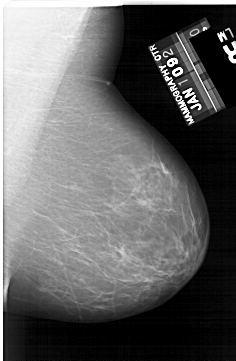

A_1634_1.LEFT_MLO

LEFT_MLO LINES 6271 PIXELS_PER_LINE 4291 BITS_PER_PIXEL 12 RESOLUTION 43.5 OVERLAY